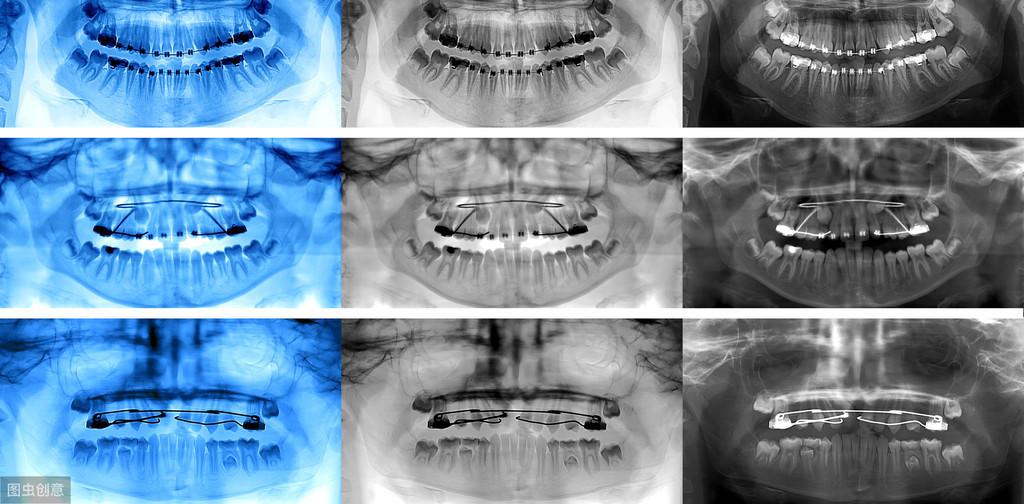

我是牙科醫(yī)生黃征難,36年從業(yè)經(jīng)歷,如果你有任何口腔問(wèn)題,歡迎關(guān)注后在主頁(yè)私信咨詢,或評(píng)論留言!可以私信牙片,我來(lái)幫你免費(fèi)問(wèn)診!拓展知識(shí):瑞士種植牙系統(tǒng)多少錢一個(gè)